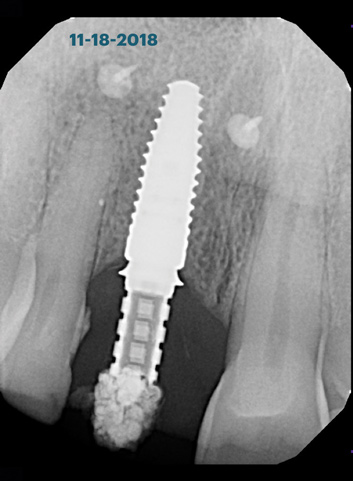

(6.) Pretreatment periapical radiograph.

Figure 6

A 56-year-old female patient was referred for the evaluation of tooth No. 8 (Figure 4 and Figure 5). A periapical radiograph indicated that the tooth had undergone apicoectomy and received an excessively long post (Figure 6), and a cone-beam computed tomography (CBCT) scan of the site revealed a lack of buccal plate bone (Figure 7).